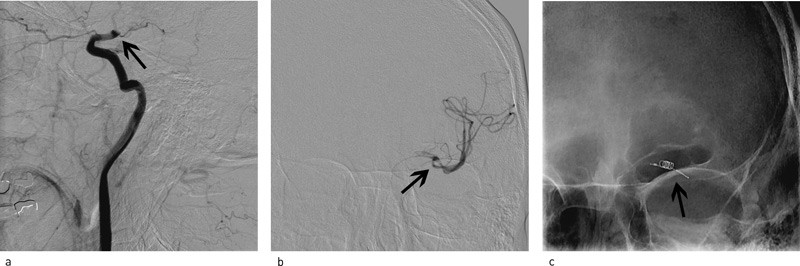

Ved cerebral angiografi ble det påvist akutt okklusjon av distale del av a. carotis interna på venstre side (carotis terminus) (fig 3a), manglende fremstilling av bakre a. comunicans posterior samt tynn første gren av høyre a. cerebri anterior. Begge carotisbifurkasjoner på halsen var normale. Ved hjelp av et trombektomikateter (MERCI-slynge, Concentric Medical Mountain View, California) ble venstre a. carotis interna, media og anterior åpnet opp (fig 3b, 3c, fig 4a, 4b). Blodgjennomstrømmingen til venstre hemisfære ble med angiografi verifisert gjenopprettet nesten tre og en halv time etter symptomdebut. Umiddelbart etter var pasienten noe mer våken og kunne med noe møye si navnet sitt (NIHSS 14). CT av hodet viste ingen blødning, men ødem i venstre hemisfære. CT dagen etter viste lavattenuerende forandringer i deler av a. cerebri medias forsyningsområde på venstre side. Han lå i flere dager i intensivavdeling. Ny vurdering angående hemikraniektomi ble aldri nødvendig. Pasienten ble overført til opptrening i slagenhet, der han fire uker etter prosedyren var i klinisk bedring.